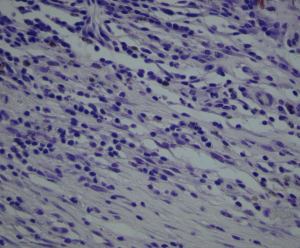

Figure 1. Immunostained surgically-excised inflammatory active CNV

A: Inflammatory active CNV with more inflammatory cells than fibrosis. (hematoxylin and eosin, 25x) B: There is VEGF expression in cells in the stroma, mainly macrophages and fibroblasts and some endothelial cells, as determined by cytologic characteristics [9]. (peroxidase anti-peroxidase, 63x) C: There are numerous cells in the stroma, mainly macrophages, expressing TF. (peroxidase anti-peroxidase, 63x) D: Negative control. (peroxidase anti-peroxidase, 63x)

B